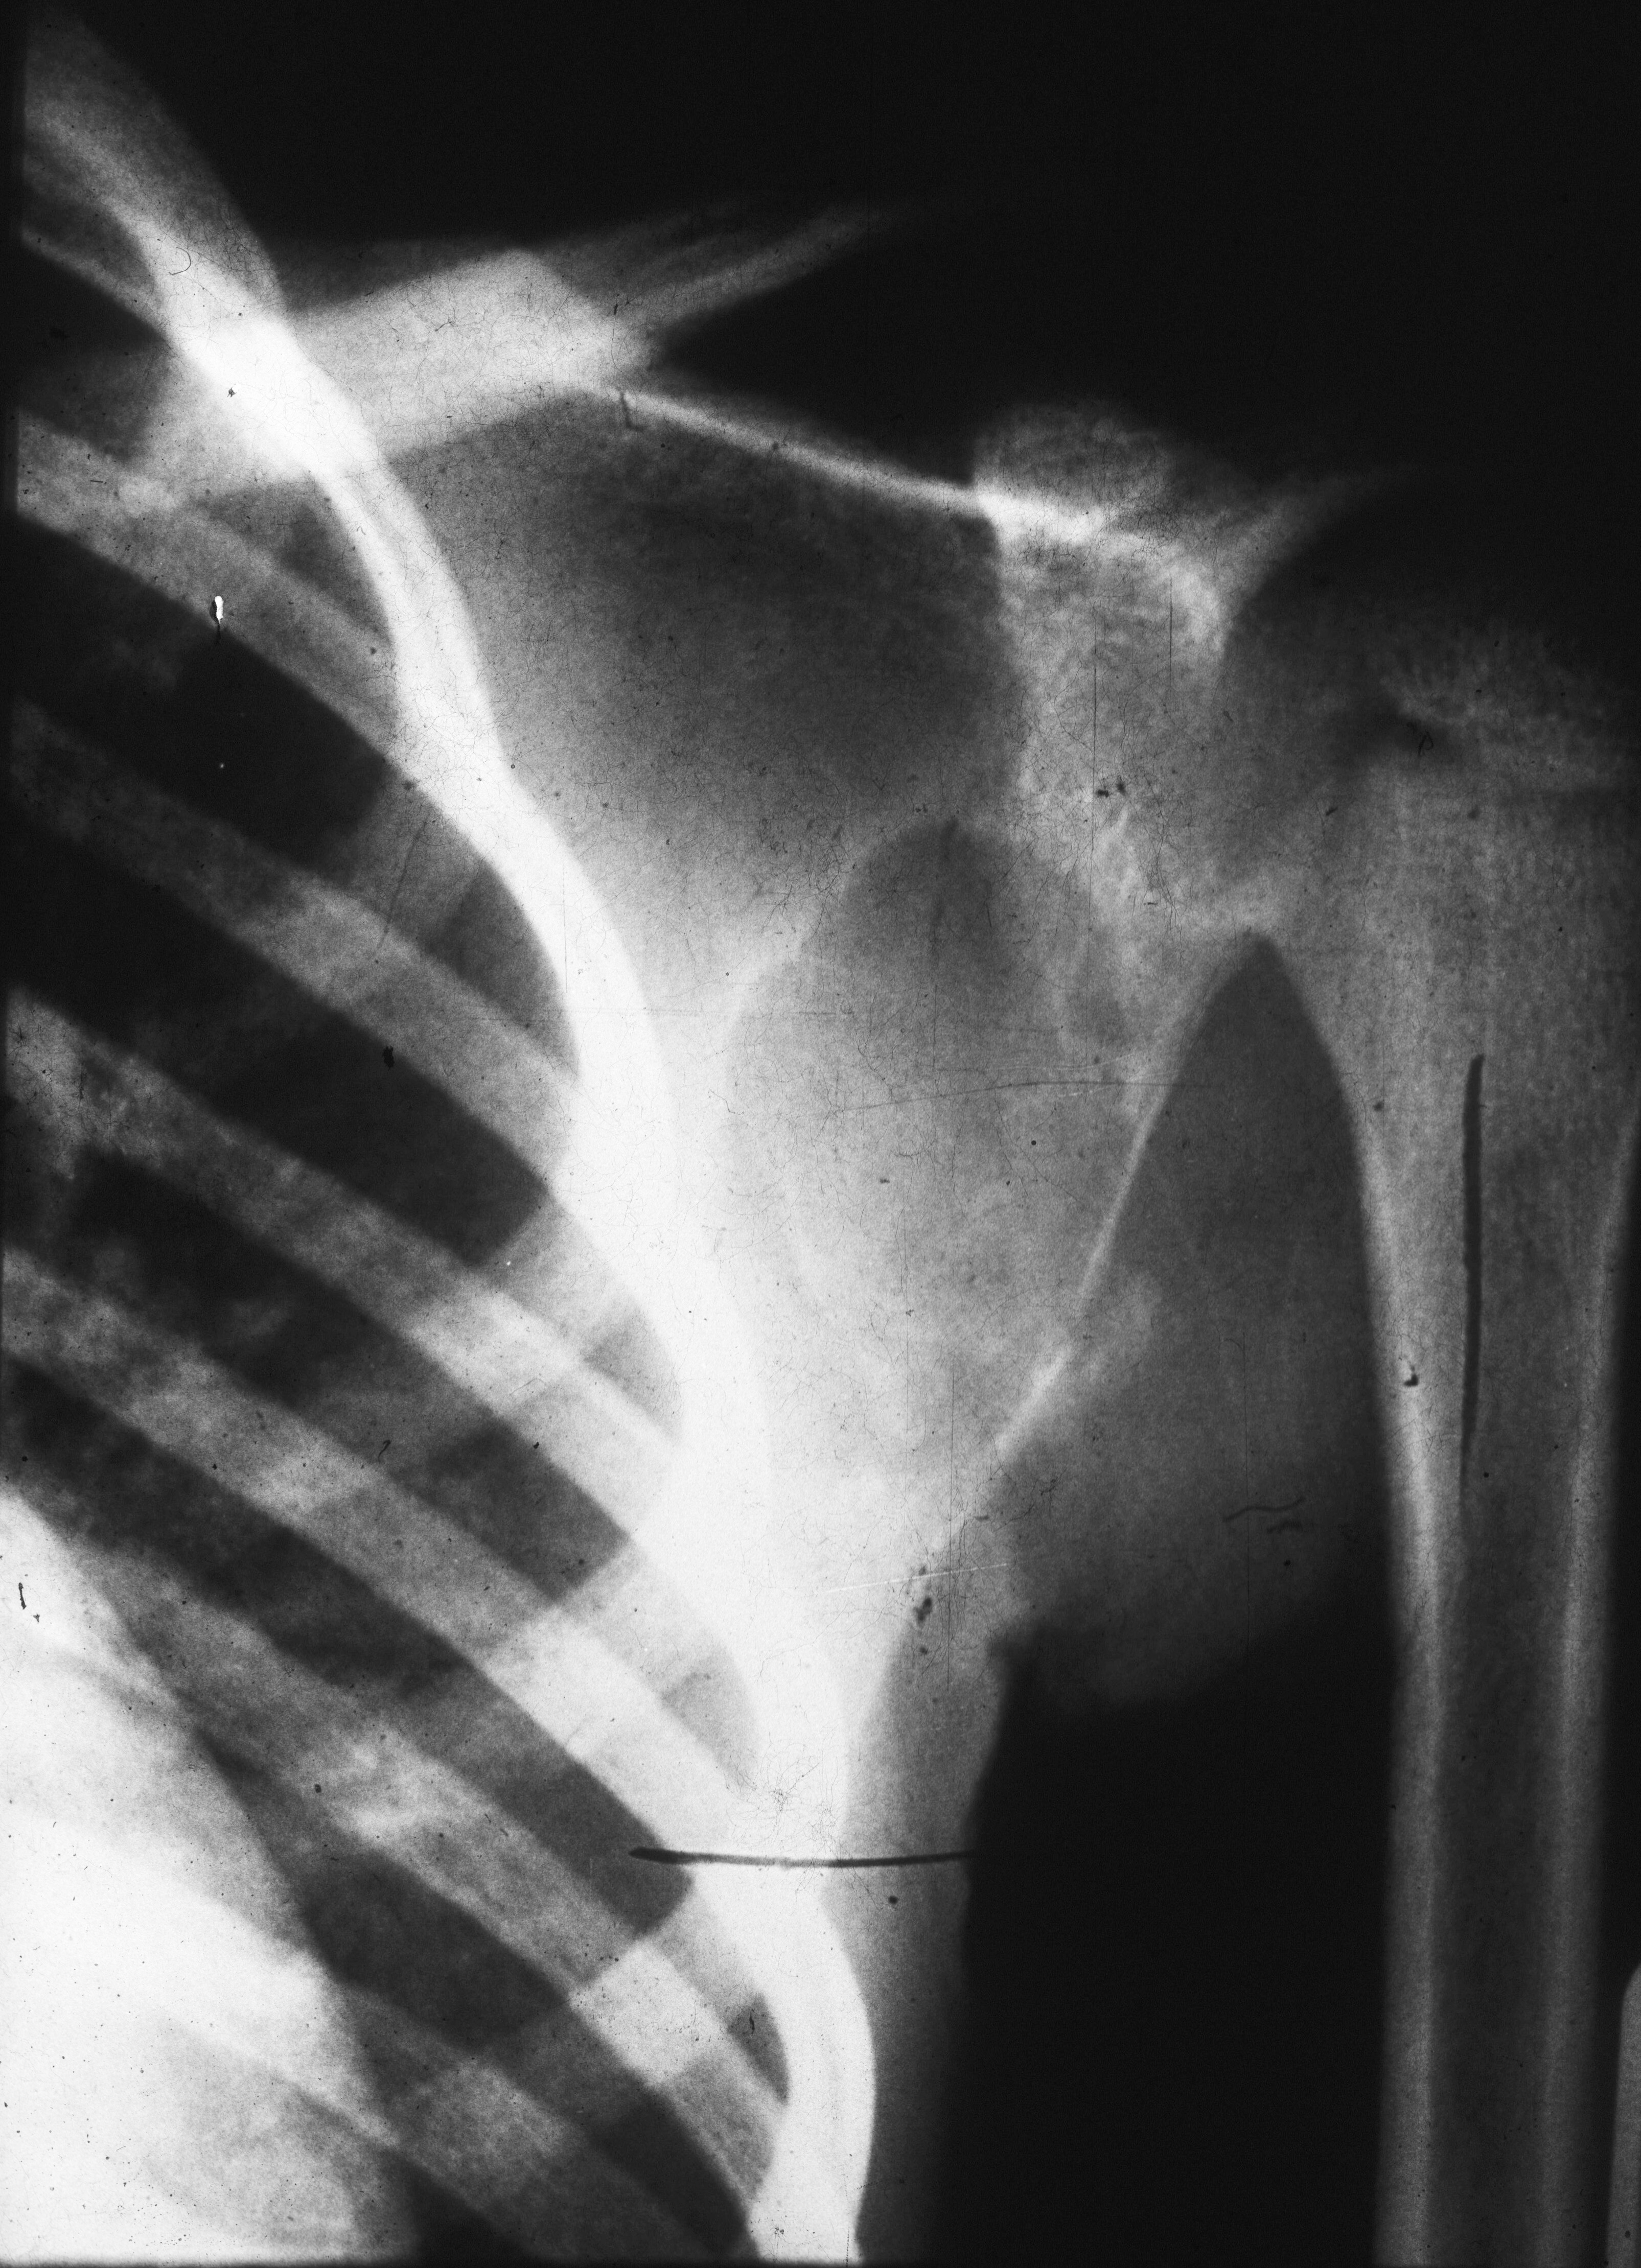

The scapular lesion may simulate aneurysmal bone cyst or show a combination of sclerosis and lysis (Figure 12).

Figure 12: FD Scapula - expanding cystic lesion.

In the humerus, a combination of osteolysis with a rind or diffuse expansion of the shaft may be noted (Figure 13).

Figure 13: FD – Humerus. Note the expanding lytic lesion in a 3 yr old .